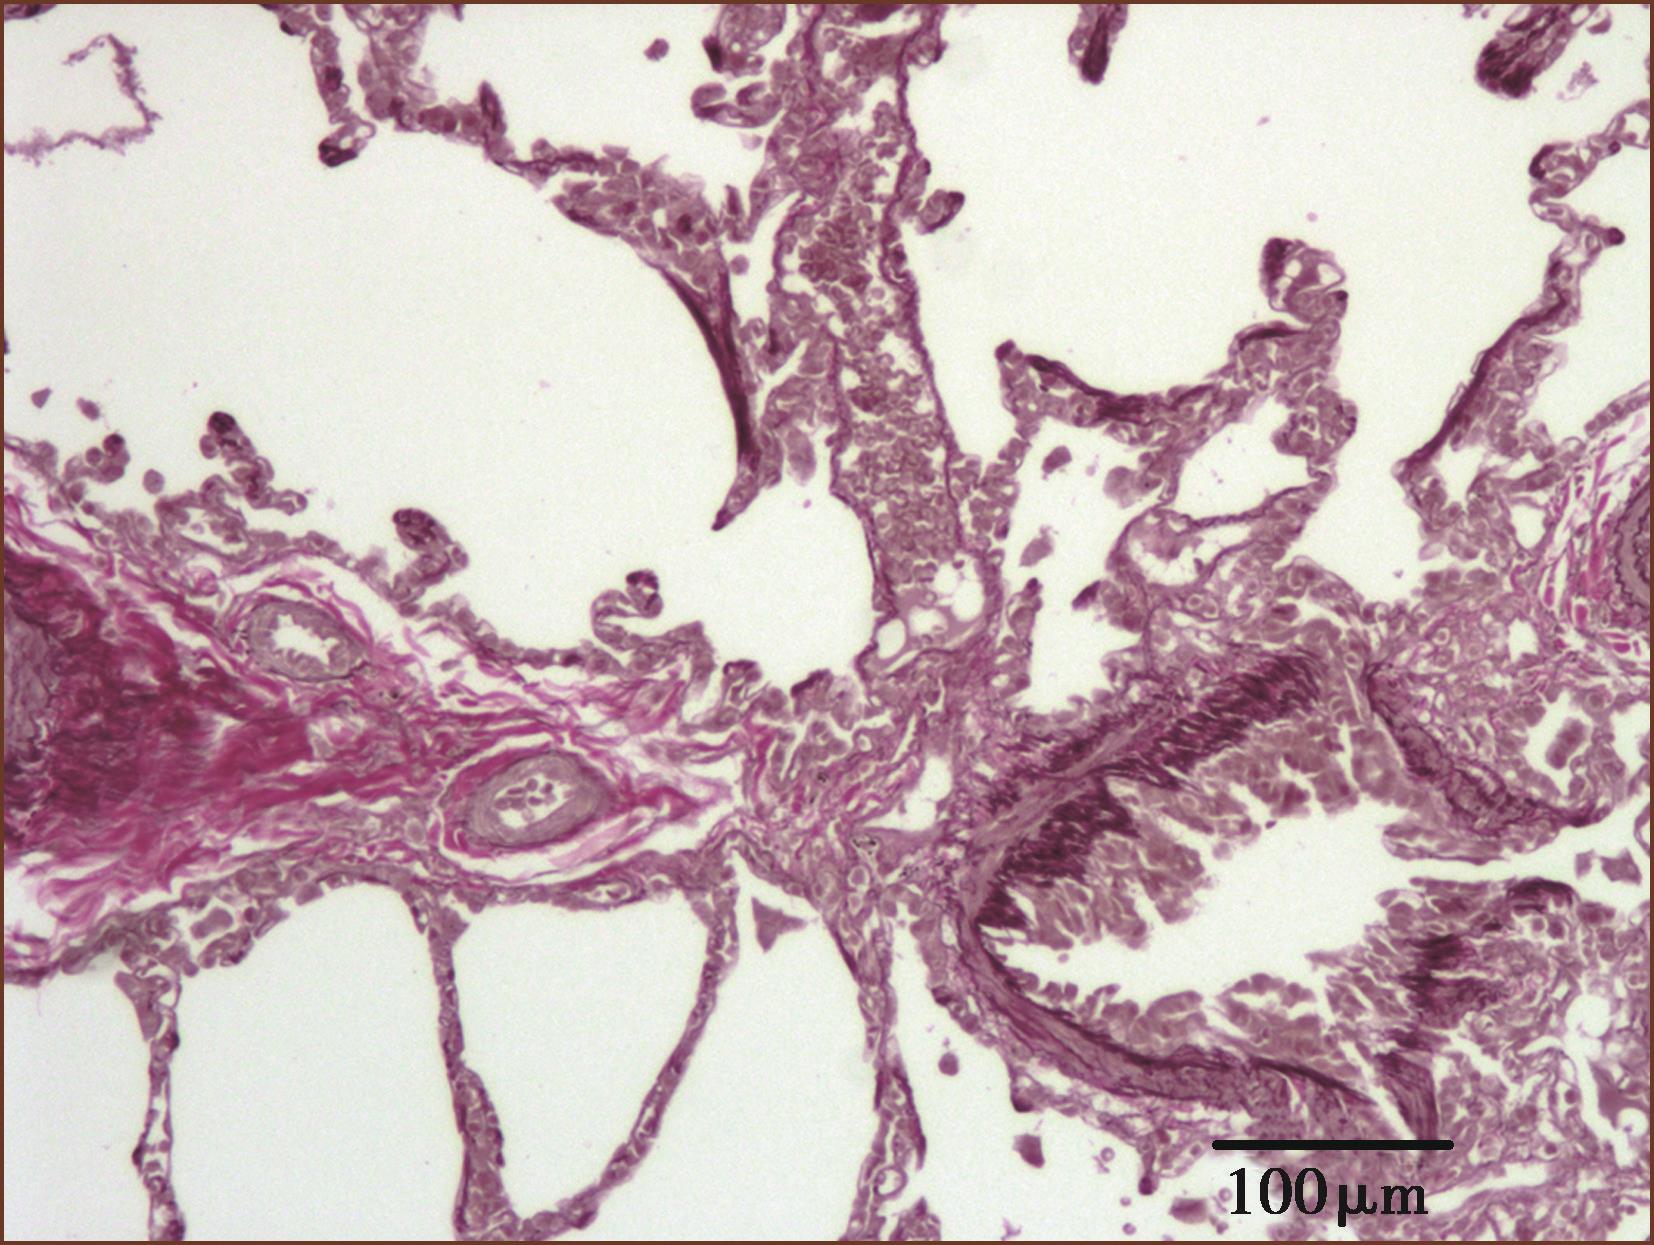

肺内肌型小动脉的外径通常为0.1~1mm,中膜肥厚即内外弹力板之间的动脉中层平滑肌细胞数量及大小的增加导致中膜厚度增加(图3-1-1)。肺小动脉平均中膜厚度大于外径的10%以上即可定为PH中膜肥厚,在成人肺动脉高压中膜厚度通常会达到15%,儿童则为25%,而肺微细动脉则可达到35%。

肺动脉高压肺小动脉中膜肥厚的另一个表现为肺微细动脉肌型化(图3-1-2)。在正常成人肺组织中,外径100μm以下的微细动脉中膜没有连续的平滑肌层。在肺动脉高压时微细动脉中膜可见连续的平滑肌层(图3-1-2)。

图3-1-1 肺小动脉中膜肥厚(ET+VG染色,中倍放大)

图3-1-2 微细动脉肌型化(ET+VG染色,中倍放大)